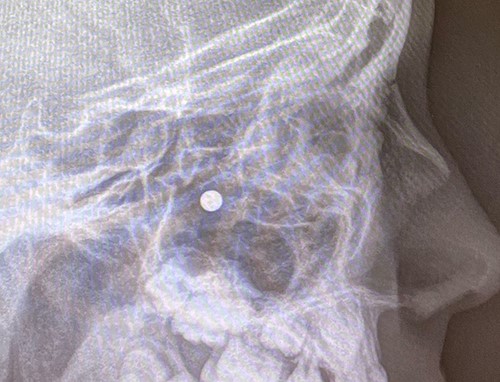

An 11 year-old male was transferred to the emergency room after being shot with a BB gun while playing. The patient’s custodian reports that he returned home with severe bleeding from bilateral nostrils which spontaneously resolved. The patient denies postnasal drip or salty taste. His medical history includes bipolar disorder and attention-deficit disorder managed with medications. On physical examination, an entry point wound is noticed in the skin of the left nasal sidewall (Figs 1 and 2). No active bleeding is noticed from anterior nasoscopy or in the posterior oropharynx exam. The rest of the head and neck examination is unremarkable. Plain X-rays performed in the emergency room confirm the presence of a metallic object in the right nasal cavity/paranasal sinuses (Figs 3 and 4). After consent is obtained, the patient is taken to the operating room and nasal endoscopy is performed. The left nasal cavity appears unremarkable. In the posterior nasal cavity, minimal bleeding and avulsed tissue is noticed after medialization of the middle turbinate. After minimal removal of tissue with pediatric Blakesley forceps, the BB bullet is visualized as lodged in the right posterior nasal cavity adjacent to the posterior attachment of the middle turbinate (Fig. 5). The bullet was then grasped with Takahashi forceps and removed after minimal endoscopic dissection (Fig. 6). Following extubation, the patient was observed for 8 h prior to discharge. During this period, no signs of recurrent epistaxis or cerebrospinal fluid rhinorrea were noticed.

In the past, non-powder guns were traditionally spring-loaded weapons that would release their projectile at a muzzle velocity (the speed of a projectile the moment it discharges from the muzzle of a gun) at less than 350 feet per second (fps). Recent advances in compressed-gas technology have increased muzzle velocities of non-powder guns to 900–1200 fps, which approximates the muzzle velocities of modern rifles with high-velocity cartridges [3]. Case series of penetrating injuries in the head and neck caused by BB and pellet guns have been previously reported [4, 5], but there are only two reports of similar injuries with BB guns in the paranasal sinuses [6, 7]. The path of the bullet is pertinent to the unusual presentation in our case: the entry point of the bullet was observed in the skin of left nasal sidewall at the level of left upper cartilage, and plain X-ray film showed the metallic bullet was located in the right nasal cavity. In the initial evaluation under the emergency situation, this raised concerns for a laterality error and mirroring of the plain X-ray image. This was readily addressed after discussion with the radiology technicians to confirm the imaging protocol was correct. After a thorough discussion of the procedure, the patient’s custodian consented to bilateral nasal endoscopy and need for possible bilateral intervention prior to proceeding to the operating room.

Although preoperative computer tomography (CT) was considered, it was deemed redundant and we elected to avoid additional radiation to the patient. When feasible, avoiding additional radiation is reasonable for pediatric patients, especially in light of a large retrospective cohort study in the Netherlands showing a higher incidence of brain tumors in children with histories of CT scans compared with the general population [8]. It has to be noted though that the decision to skip the preoperative CT was dictated mainly by the clinical presentation (no signs of cerebrospinal fluid leak and no active epistaxis) and the plain X-ray findings suggesting the bullet was a relatively safe distance from the skull base and the orbits. Had concerns about involvement of the latter been raised, a CT would have been additionally ordered, as it also provides the opportunity for intraoperative navigation.